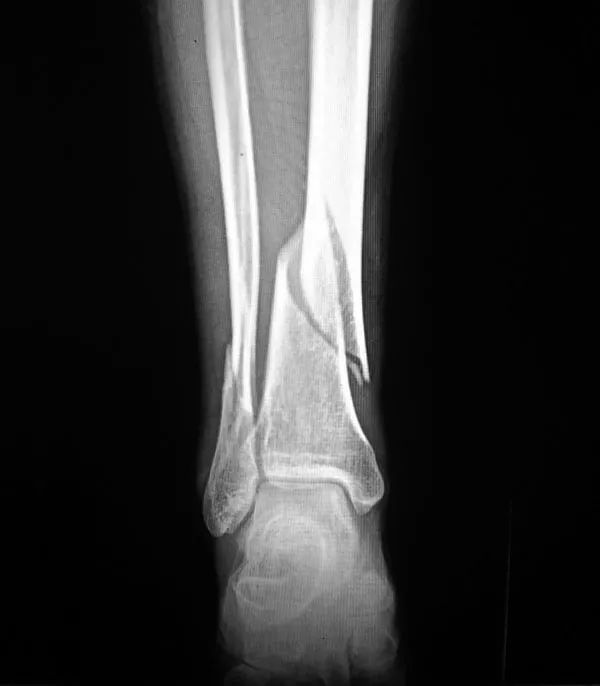

2、骨折:骨質(zhì)疏松癥最常見的并發(fā)癥是骨折,輕微外力即可導(dǎo)致骨折,60歲以上老年人骨質(zhì)疏松并發(fā)骨折者高達(dá)12%。多見咳嗽打噴嚏時(shí)、彎腰屈伸撿東西、回頭轉(zhuǎn)身及摔倒等易發(fā)生骨折。骨量丟失20%以上時(shí)易發(fā)生骨折,輕者可使活動(dòng)受限,重者須長期臥床,給社會(huì)和家人造成很大負(fù)擔(dān)。老年人骨折可引發(fā)或加重心腦血管并發(fā)癥,導(dǎo)致肺感染和褥瘡等多種并發(fā)癥的發(fā)生,嚴(yán)重危害老年人的身體健康,甚至危及生命,死亡率可達(dá)10%~20%。